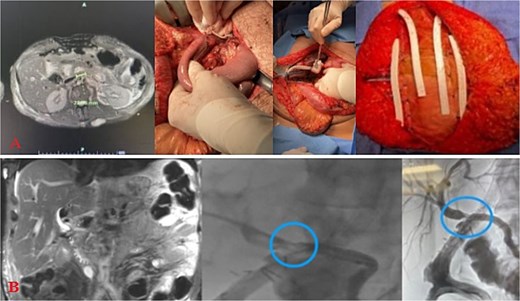

Massive transfusion protocol was initiated, and he was taken to the operating room for an emergent exploratory celiotomy. Upon entrance into the abdominal cavity, a 10 cm hematoma, along the transverse colon consistent with a mesenteric arterial hemorrhage, was identified and rapidly controlled (Fig. 1A). A Cattell-Braasch maneuver was employed, mobilizing the right colon, and a Kocher maneuver to fully explore the duodenum, revealing a AAST Grade II D2 injury that was repaired in 2 layers (Fig. 1B). The pancreatic head and tail had AAST Grade II injuries with multiple arterial bleeds that were controlled with suture ligation and argon beam coagulation (Fig. 1C).

Index operation. A: Transverse colon hematoma. B: Duodenal (D2) injury. C: Pancreatic head and tail vascular injury. D: Common bile duct and intraoperative cholangiogram through the common bile duct and cystic duct.

On initial inspection, the GB infundibulum was contused, and there was bile staining along the porta hepatis. The common bile duct (CBD) was identified and appeared grossly normal. However, due to the proximity of the pancreatic head injury and bile staining, we performed an intraoperative cholangiogram (IOC) through a mid-portion CBD needle ductotomy, to spare the GB as a potential conduit if a biliary repair was required. The initial IOC did not reveal an injury to the CBD and did not demonstrate extravasation of contrast (Fig. 1D). The needle ductotomy was closed with a running 3–0 Monocryl stitch. As we were concluding the damage control laparotomy a persistent, mild, bile staining within and along the porta hepatis, was noted. The possibility of a more proximal extrahepatic bile duct injury was raised as the common bile needle ductotomy closure remained intact.

Further inspection of the GB and proximal extra biliary ductal system revealed a large GB bed hematoma and partial avulsion of the GB (AAST Grade 3). Due to the risk of delayed GB ischemia, a cholecystectomy, and an additional IOC via the cystic duct this time was performed to rule out a more proximal ductal injury and a possible bile leak from the prior IOC distal needle ductotomy. The more proximal and distal IOC did not reveal a bile leak, however, the more proximal ductal structures were not optimally demonstrated. No further bile staining was noted. The abdomen was irrigated, and 4 Jackson-Pratt (JP) drains and an AbThera™ Advance Open Abdomen Dressing (3 M, Saint Paul, MN, USA) were placed. The patient was stabilized and transferred to the intensive care unit (ICU) for further resuscitation, on triple antibiotics, pantoprazole, and a somatostatin drip.

The patient stayed a total of 77 days at the hospital with around 54 days spent in the ICU. He was initially in ICU care for his extensive traumatic and complicated recovery. On POD1–3 increased bilious output was noted from a JP drain. He was taken back to the operating room (OR) on POD3 for re-exploration. There was a small contained biliary collection of ~2.23 cm in the GB fossa without active bile leak noted, viable bowel, and intact duodenal repair. The patient underwent placement of a gastrostomy and feeding jejunostomy tubes, an appendectomy, and abdominal wall reconstruction with Ovitex. He returned to the OR on POD7 for frank blood noted in another JP drain where a persistent gush of blood was noted at the GB fossa. This was repaired with multiple clips and figure of 8 sutures. The abdomen was packed and the Abthera wound vac was replaced. Repeat re-exploration on POD8 noted continued hemostasis, but there remained bile near the porta hepatis and two additional JP drains were left in the region of concern. He recovered well for the consequent days with stabilized bilirubin levels (Fig. 2A). However, on POD20, it was noted that he had increasing bile output of over 1 L over 24 hours. The bile was consequently fed back through his J-tube, and on POD25, a hepatobiliary iminodiacetic acid scan (HIDA) scan failed to demonstrate the leak and an initial ERCP attempt failed secondary to a duodenal diverticula. On POD27, magnetic resonance cholangiopancreatography (MRCP) demonstrated a common hepatic duct stricture. ERCP was successful in cannulation of the ampulla on POD32 with continued lack of contrast extravasation at the distal common bile duct. On POD35, percutaneous transhepatic cholangiography drain was placed to relieve concerns of a leak. On POD54, interventional radiology and gastroenterology successfully completed a ERCP rendezvous procedure to place a biliary stent over the area of stricture. (Fig. 2B) This intervention successfully reduced the amount of bilious and overall JP output. On hospital Day 77, he was consequently discharged with all drains removed and tolerating a regular diet.

Injury sequelae and interventions. A: Re-exploration due to bilious changes. B: Delayed presentation of common hepatic duct stricture with rendezvous procedure.